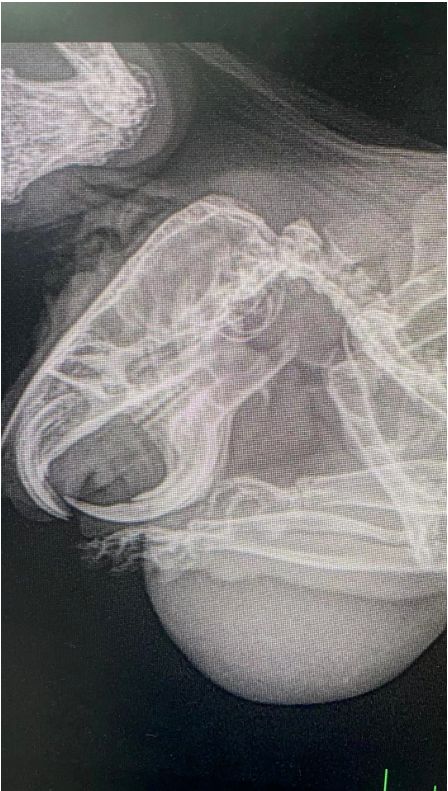

症候描述:仓鼠团团下颌部半月内长出一块1cm*1cm大小肿物,精神状态良好,食欲尚可,大小便正常。

初诊:触诊为实质性肿物,细针抽吸并未见血或脓性物质,初步判定为下颚皮下肿瘤。

检查确诊:建议主人给其拍X光片、血常规、生化、肿瘤样本送检,经过沟通主人要求只进行X光片拍摄。